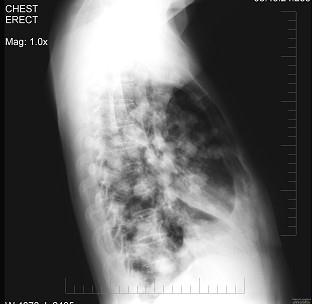

问题 女性,53岁,胸闷乏力数月,偶感胸痛,不发热,X线检查如图,最可能的诊断是 ( )

选项 A.原发性肺癌 B.亚急性血行播散型肺结核 C.肺转移瘤 D.细支气管肺泡癌 E.胸腔积液

答案 C